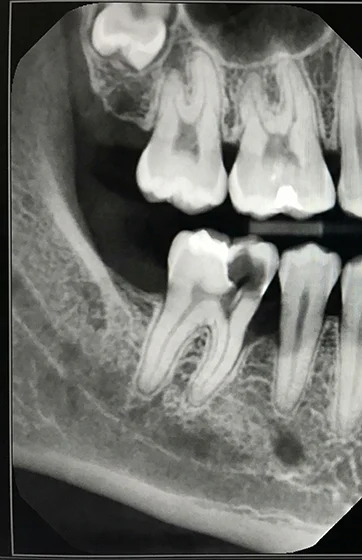

Brush twice a day with fluoridated toothpaste and floss gently around the filled tooth to limit plaque buildup. Avoid chewing ice or hard candies, and reduce sugary snacks to lower the risk of new decay around the filling. If sensitivity lasts or you notice a crack, contact us promptly. With steady care, dental fillings can last for many years.